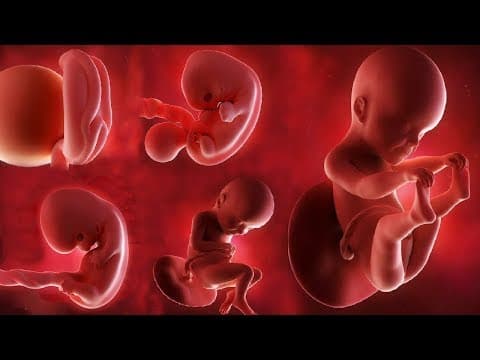

- 3D/4D/5D ultrazvuk i fetalna medicina

• 2D ultrazvuk = standardna ravna slika (sve poliklinike imaju) • 3D ultrazvuk = trodimenzionalna slika fetusa (detaljnije vide se anomalije) • 4D ultrazvuk = 3D slika u pokretu (vidite fetus kako se mijenja u realnom vremenu) • 5D/HD Live ultrazvuk = najnaprednija tehnologija s detaljima kao fotografija U Poliklinici Harni koristimo 3D, 4D i 5D ultrazvuk, što nam omogućava ranom otkrivanju anomalija i pružanju roditeljima jasne slike bebe prije poroda.